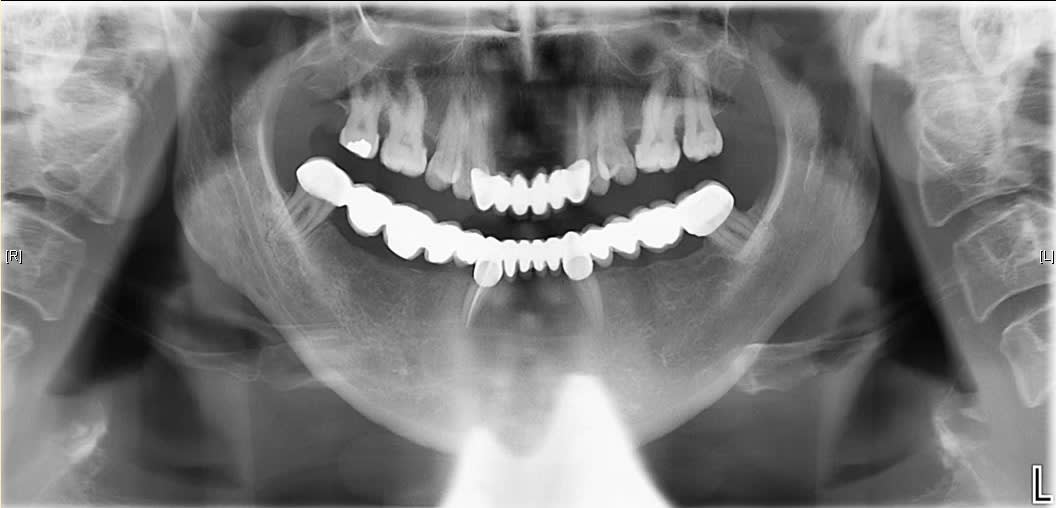

Osons ! Osons !

En place depuis 10 ans. Aucune mobilité.

Je vous laisse admirer les belles courbes occlusales.